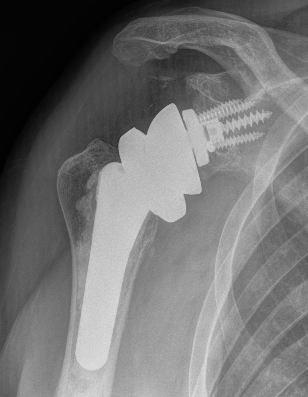

Shoulder Hemiarthroplasty Rotator Cuff FailureTSR Superior EscapeaTSA failed cuffTSR Failed Rotator CUff

Overstuffed aTSARevision to revTSA